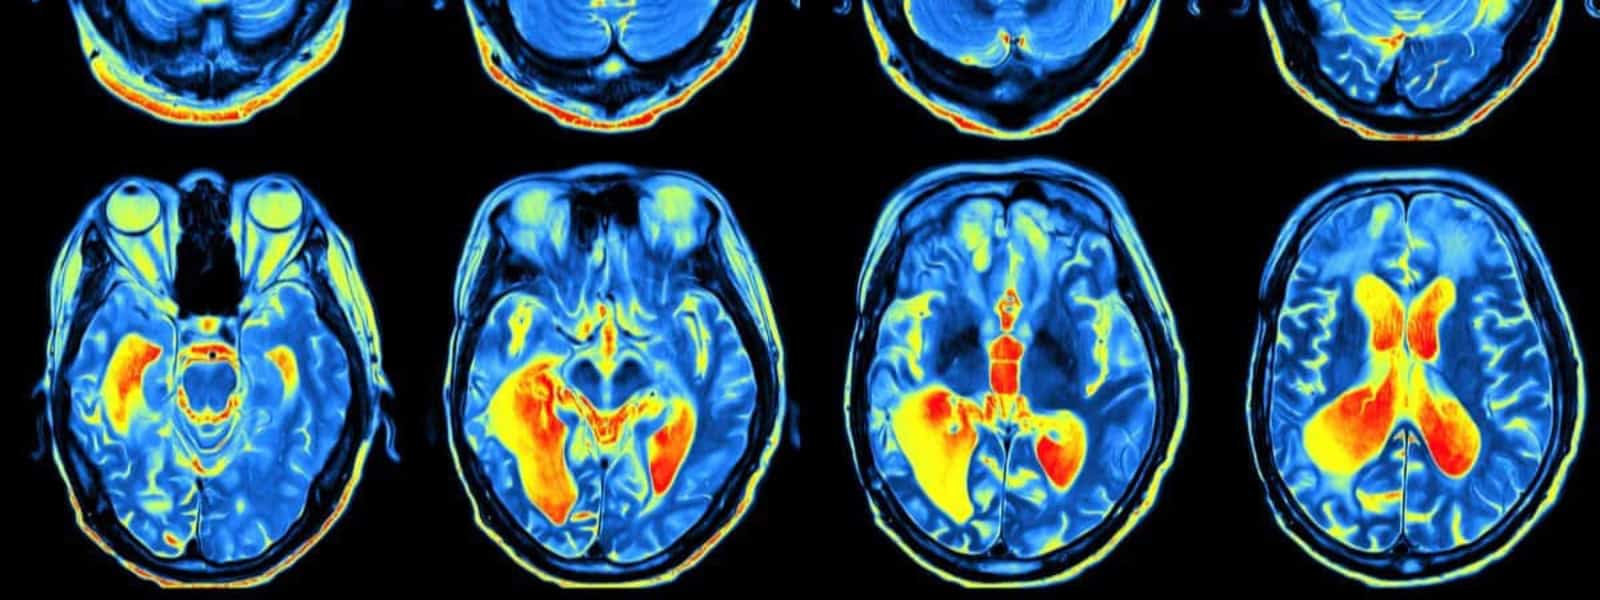

Magnetic resonance images, bone-density scans, carotid artery ultrasound and more